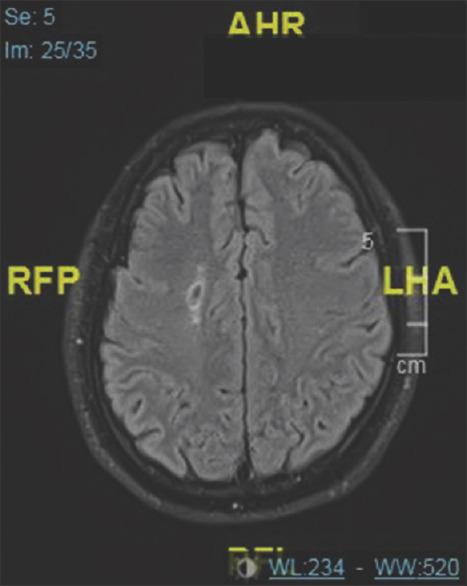

Conversion disorder (CD) is a neurological symptom that is not related to any medical or neurological disease. Symptoms can range from sensory complaints to loss of consciousness. Psychological stressors such as surgery and anesthesia are considered a precipitating factors. Early diagnosis is crucial to prevent unnecessary interventions. Here, we report a case of a patient who developed CD upon emergence from general anesthesia.

转换障碍(CD)是一种与任何医学或神经疾病无关的神经症状。症状范围可从感觉主诉到意识丧失。诸如手术和麻醉等心理应激源被认为是促发因素。早期诊断对于防止不必要的干预至关重要。在此,我们报告一例患者在全身麻醉苏醒后出现转换障碍的病例。